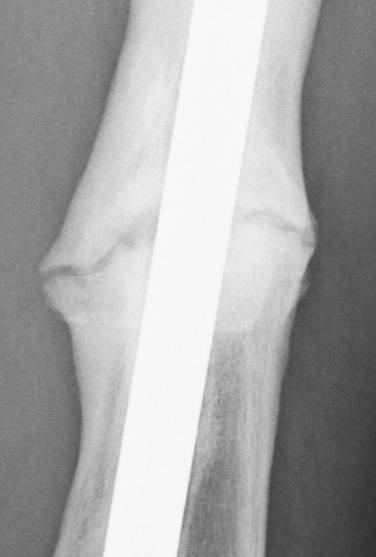

June 22, 2010 X-ray update

Forive me people for I have sinned. It has been two years since my last update. But seriously, there is much improvement to report. Based on activity and how it feels things are progressing very well. The x-rays also show more bone growth which adds to the good sign.

Feb. 21, 2008 jUNE 22, 2010